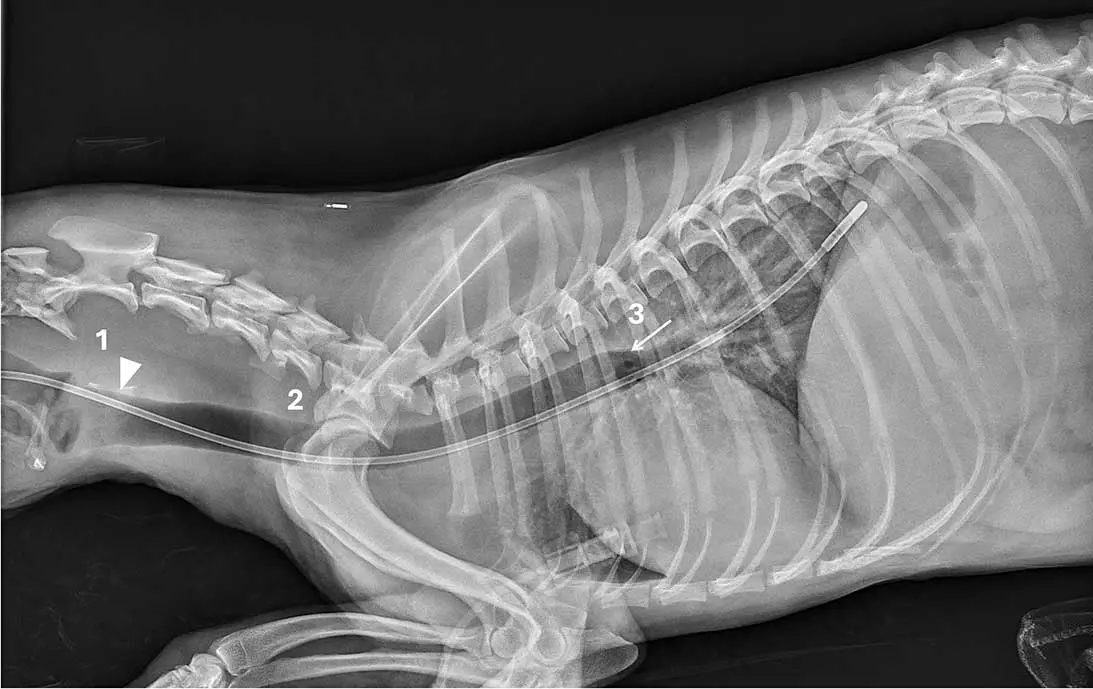

Case two

This lateral cervical and thoracic radiograph of a dog includes the larynx (Figure 2). The tube is superimposed over the laryngopharynx (1) and tracheal lumen, passing through the laryngeal lumen (arrowhead), the rest of the tracheal lumen (2) and extending to the carina (3; arrow) before following a caudodorsal bronchial path.

Interpretation. Incorrect tracheal placement. None of the three criteria are met, as the tube does not pass dorsal to the lamina of cricoid cartilage or the carina, and it completely overlaps the tracheal lumen throughout its course. The tube was immediately removed and correctly repositioned.